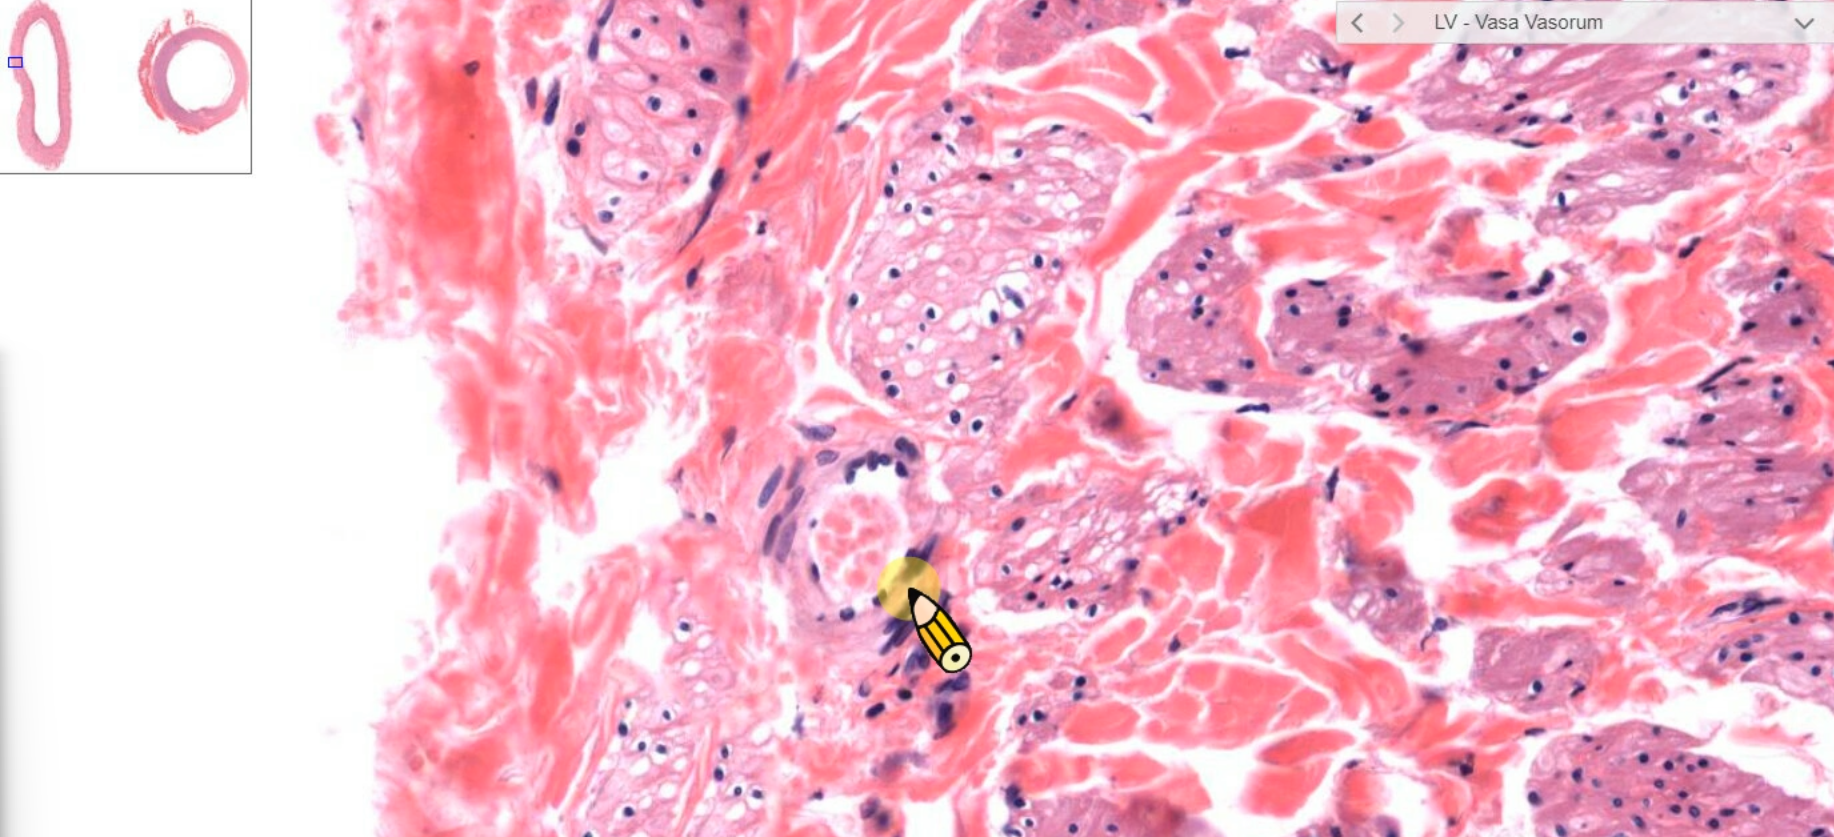

tunica adventitia

2. vasa vasorum(血管滋養管)

fibroelastic CT vasa vasorum

vasa vasorum